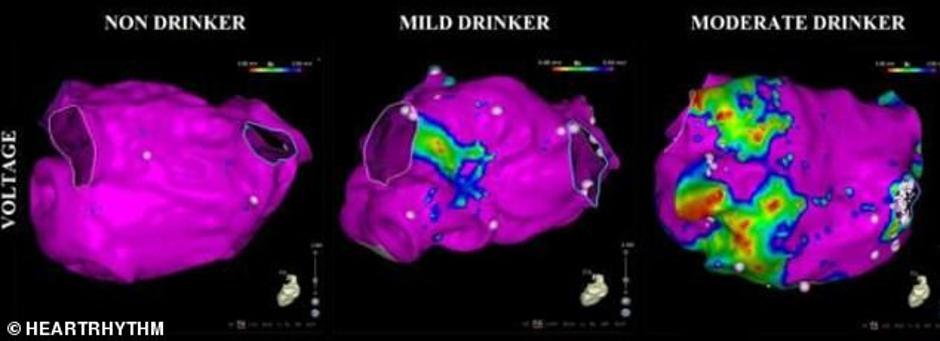

Skenovi srca, koje su snimili znanstvenici iz bolnice Alfred u Melbourneu, pokazuju kako električni impulsi putuju kroz atriju, mjesto gdje krv dolazi do srca. Podijelili su 75 ispitanika na kojima su bazirali ovo istraživanje u tri skupine; ovisno o tome koliko alkohola su rekli da konzumiraju. Inače, električni su impulsi ključni za rad srca jer ih kontroliraju čvorovi kojima su vezani za živčani sustav, a kojemu šalju informaciju kada se srce opušta a kada stišće.

Na skenovima je srce onih koji uopće ne piju svijetloružičaste boje koja pokazuje zdravo srčano tkivo kroz koje putuju impulsi. Srce onih koji ‘piju umjereno’ ima zakrpe u zelenoj boji, koja pokazuje mjesta na kojima su impulsi slabiji. Kao ‘umjerene konzumente’ su uzeli one koji piju između osam i 21 alkoholnog pića tjedno, točnije 14 u prosijeku.

No i 14 čaša alkohola je daleko više od onoga što preporučuje Nacionalni centar zdravlja u Australiji koji kaže da je umjerena doza oko devet čaša vina, odnosno sedam krigli piva tjedno. No čak i oni koji se drže toga i piju do deve čaša vina tjedno su na skenovima imali ‘zakrpe’ zelene boje, odnosno oštećeno tkivo srca.

Skenovi su tako dokazali da, kako je rekao i voditelj studije dr. Peter Kistler, čak i umjerena konzumacija alkohola može utjecati na impulse odgovorne za pravilan rad srca, a promjene koje se kod njih vide objašnjavaju zašto oni koji redovito piju često imaju problem sa srcem baš na mjestu gdje krv prolazi kroz njega.